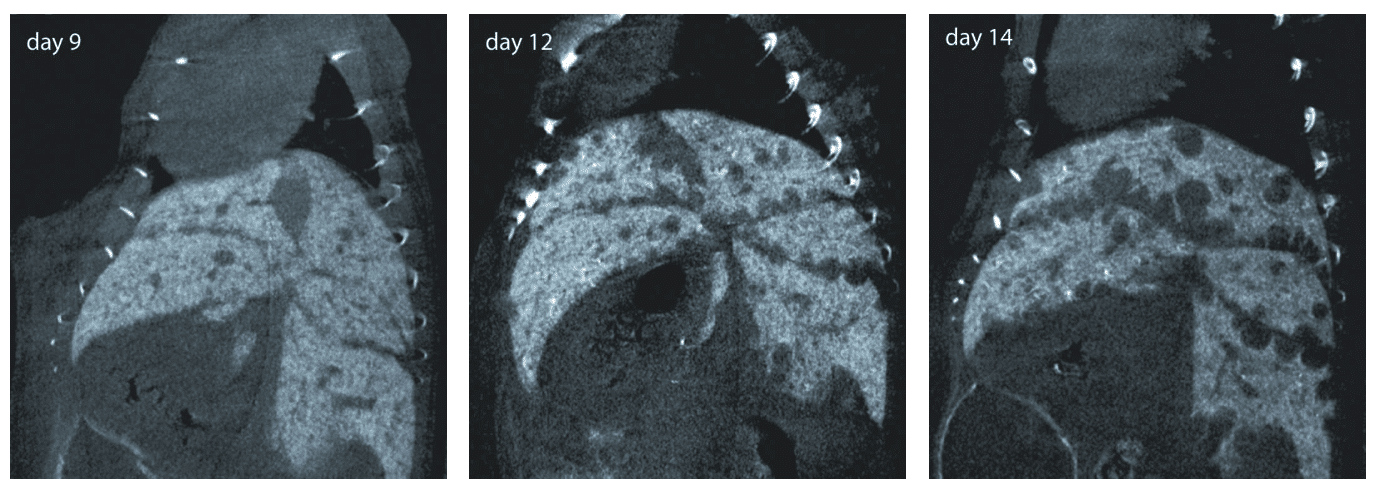

Preclinical Imaging Validation

Imaging studies demonstrate clear opacification of liver lobes and metastases in murine models following a single injection. Longitudinal monitoring confirms sustained enhancement suitable for quantitative assessment of lesion progression and therapeutic response.

Following administration, ExiTron™ nano 6000 accumulates in liver parenchyma, producing high contrast between healthy tissue and surrounding structures. This contrast facilitates clear identification of liver tumors and metastatic lesions, supports quantitative measurement of tumor burden, and enables monitoring of morphological changes over time. The low injection volume and favorable cardiovascular tolerability make the agent suitable for animals with limited physiological reserve.

ExiTron™ nano 6000 is applied in micro CT studies targeting liver morphology, tumor detection, metastasis tracking, and longitudinal disease progression. Its long hepatic retention allows researchers to conduct repeated imaging from hours to weeks post injection, supporting robust experimental workflows in oncology, hepatology, and pharmacological studies.